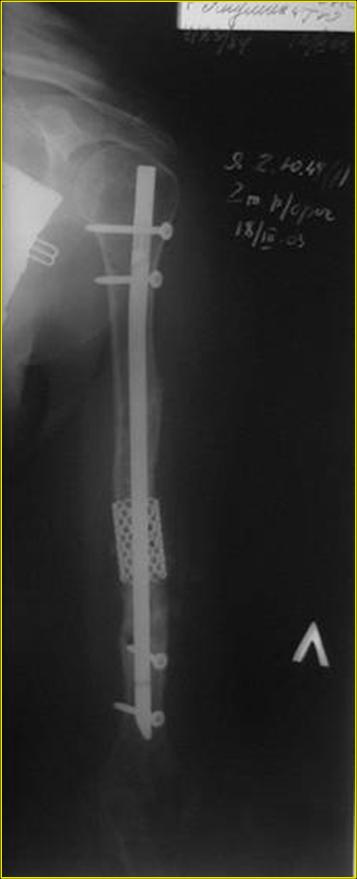

Рентгеновская версия реконструкции. хронология:

после операции, 2 мес. после операции, через 1 год

Движения в полном объеме восстановлены к 2 мес. после операции. Если надо могу показать мультик. Сейчас уже прошло более 3 лет, больная не

показывается. Успехов ЛАФ.